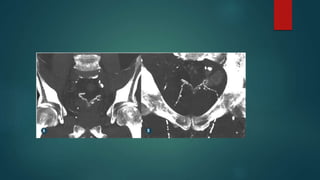

INVASÃO SECUNDÁRIA TUMOR DE

PRÓSTATA